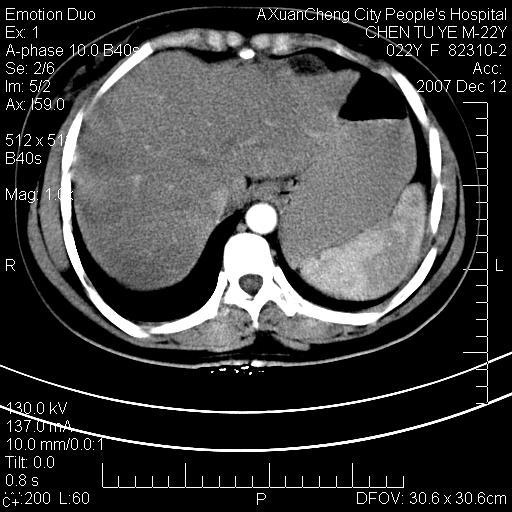

超声提示肝右前叶占位,约2.5cm.

各位战友看看病灶在什么地方,可是右前叶进肝裂部低密度影,平扫ct值约10以下,增强后增高明显

1 脾大,慢性肝损伤. 2 肝脏脂肪侵润.  3 你所指的部位疑点,我没看出有问题.

脂肪肝.楼主所指部位不考虑异常,为肝圆韧带影.

不均匀脂肪浸润,版主所说的病灶为肝园韧带服着点。

考虑肝圆韧带。